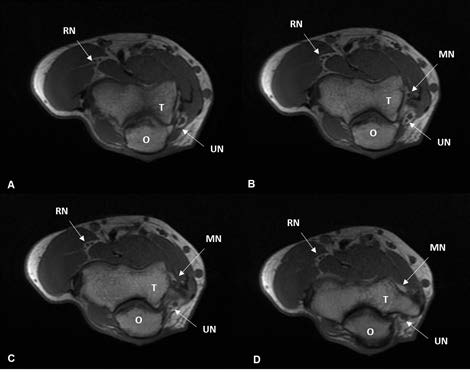

A 45-year-old woman, housekeeper, was sent to the Rheumatology appointment for pain and functional limitation in extension and flexion movements of the fingers, accompanied numbness in the 4th and 5th finger of the right hand. This clinical depiction had 2,5 years of evolution, with progressive worsening. The physical exam showed pain at palpation of ulnar nerve in the ulnar fossa of the right elbow. Blood tests and electromyography studies did not show any significant changes. Ultrasonography of the elbow revealed no changes of the median and radial nerves. The Ulnar Nerve (UN) presented without any anomalies in its entire course, except being bipartite in a small portion immediately proximal to the ulnar fossa, returning then to its unique configuration. (Fig. 1). This anatomic variation was then confirmed by Magnetic Resonance Imaging (MRI) as illustrated in Figure 2. The patient was referred to Plastic Surgery and submitted to an ulnar nerve surgical decompression at proximal level. Two weeks after surgery a sustained marked improvement of the numbness was confirmed.

Figure 2: Right Elbow MRI T1 Wei- ghted Axial Cut: ulnar nerve at different levels, going from distal to proximal (2A to 2D). It is possible to observe the bi- partite ulnar nerve in a small portion of its path (2B and 2C) and then it returns to its unique configuration (2D). Abbreviations: MN - Median Nerve, O - Olecranon process, RN - Radial Nerve, T - Trochlea, UN - Ulnar Nerve.